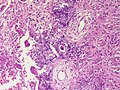

Chondroblastoma. H&E stain. | |

| LM | abundant (chondroid) extracellular material, chondroblasts (variable nuclear morphology (ovoid, folded or grooved), moderate-abundant eosinophilic cytoplasm), +/-calcifications surrounding the cell nests ("chickenwire" appearance) - classic feature, +/-giant cells |

- Abundant extracellular material - pink on H&E stain - looks vaguely like cartilage.

- Sometimes described as 'immature cartilage' (very narrow DDX for this type of cartilage)

- Chondroblasts:

- Nuclear morphology variable: ovoid, folded or grooved.

- Moderate-abundant eosinophilic cytoplasm.

- +/-Calcification surrounds the cell nests ("chickenwire" appearance) - classic feature.

- Cell nests have a thin pale blue rimming.

- +/-Giant cells.